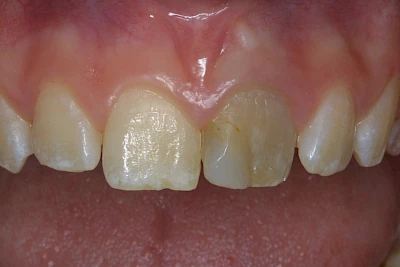

- Durch übermäßige Fluorideinlagerung in der Zahnreifung (mehrere Zähne, weißlich-fleckig)

Gerade bei Kindern und Jugendlichen werden zunehmend häufiger bräunliche Verfärbungen mitunter auch mit Formveränderungen (die Oberfläche ist rauh oder zerklüftet) der Zähne beobachtet. Meist sind Schneidezähne oder Backenzähne betroffen. Dies könnte ein Hinweis auf sogenannte Kreidezähne (MIH: Molaren-Inzisiven-Hypomineralisation) sein.